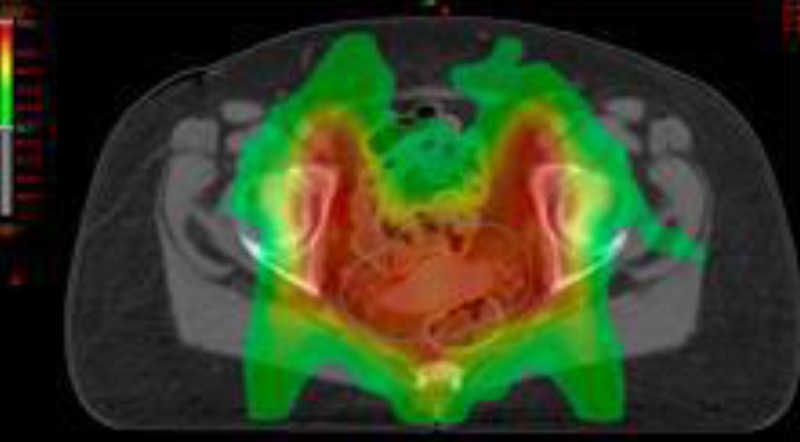

La radioterapia de intensidad modulada (IMRT) es una forma avanzada de RTC-3D capaz de crear distribuciones de dosis alrededor de volúmenes blancos complejos e irregulares. A diferencia de la RTC-3D, la IMRT utiliza haces de radiación de intensidad no uniforme. La optimización de dosis con IMRT se basa en la planificación inversa. Se prescribe primero la distribución de dosis deseada en el volumen blanco y OARs. Luego el planificador converge a la opción propuesta. La modulación de la intensidad del haz se consigue con moduladores o variando la apertura del colimador multiláminas del acelerador lineal. La IMRT permite administrar con seguridad la dosis de irradiación, reduciendo el riesgo de toxicidad aguda y tardía en comparación con la RTC-3D (fig. 2).